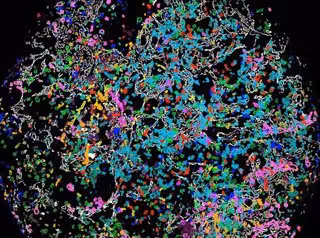

Imagen de un tumor

INCLIVA

Para realizar este patrón se ha utilizado el análisis de imagen digital microscópica y cuantificado elementos de la matriz extracelular. "Gracias a estos patrones se puede intentar reproducir el patrón poco agresivo en tumores con mayor agresividad. Si no podemos eliminar el cáncer totalmente, podemos convertirlo en una enfermedad crónica intentando que el tejido celular de los tumores más graves se asemejen al de los tumores menos agresivos para que el paciente responda de manera positiva a la terapia", concluye la doctora.